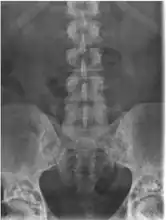

It is a genetic disorder associated with LEMD3.[6][7] It is inherited in an autosomal dominant manner.[2] In a very few, X-rays may show several areas of compact bone.[1] Conditions that may appear similar include tuberous sclerosis, pseudoxanthoma elasticum, neurofibroma, and lipoma, among others.[1]

• X-ray